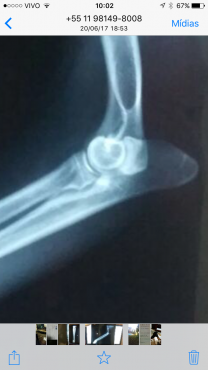

Referimos um paciente Bernese, macho, 11 meses que apresentava claudicação intermitente em membro torácico direito. Ao exame ortopédico notou-se dor diurante a extenção e rotação do membro. Realizamos Rx simples que evidenciou esclerose em região medial de ulna e na Tomografia computadorizada fechamos diagnostico para FPCM. Procedemos a cirurgia para remoção do fragmento e curetagem local. O pacente durante o pos imediato já iniciou o paioi sem claudicação e retomou suas atividades diárias normalmente em uma semana de pós operatório.